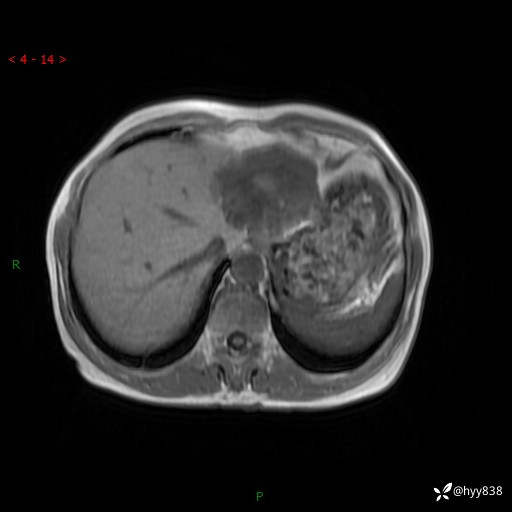

老年女性,偶然发现肝脏占位,综合各个序列,你考虑什么---结果公布

主诉:发现肝脏占位性病变2天

简要病史:患者2天前因“腰疼”至当地医院就诊时发现肝脏左叶占位性病变,无发热、畏寒,无皮肤黄染,无腹痛、腹泻,无恶心、呕吐、厌油等不适,今进一步诊治遂来我院就诊,门诊以“肝脏占位性病变性质待查”收入我科。 起病以来,患者精神、睡眠一般,饮食欠佳,二便正常,体力、体重无明显减轻,

临床诊断:肝占位

肝脏MRI平扫(同反相位)

T2WIfs+DWI

增强(动脉期+静脉期+延迟期)